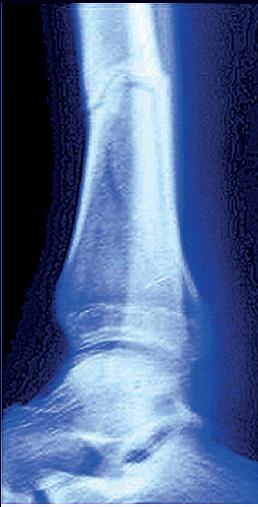

LESIONI E FRATTURE

OSSEE

Le fratture possono verificarsi a qualsiasi età. I bambini sono particolarmente a rischio, a causa delle loro attività e del fatto che le loro ossa sono in fase di crescita. Anche gli adulti di età superiore ai 60 anni sono esposti a maggior rischio, poiché le cadute causate dalla perdita di equilibrio o della vista diventano più comuni e le ossa sono più fragili.

Le fratture del polso e dell’avambraccio sono comuni perché istintivamente cerchiamo di proteggere la testa quando cadiamo. Anche le fratture vicino all’articolazione dell’anca, come il collo del femore e il bacino, sono comuni nelle persone anziane. Questi sono siti tipici di fratture causate dall’osteoporosi.

Non tutte le lesioni ossee richiedono un trattamento. Le fratture piccole e non complicate, come quelle capillari, di solito guariscono da sole. Tuttavia, spesso è necessario un trattamento specifico, soprattutto se i frammenti ossei sono spostati o il tessuto circostante è danneggiato. In queste fratture complesse, i frammenti ossei vengono riposizionati chirurgicamente

utilizzando placche, viti o chiodi. Se un intervento non è necessario, l’osso interessato viene immobilizzato con un gesso o una stecca.

Nella migliore delle ipotesi, l’osso rimane completamente intatto dopo la ricrescita ed è in grado di sostenere di nuovo il peso. Questo grazie a cellule ossee specializzate che aumentano significativamente la loro attività quando si verifica una frattura. Nel tentativo di riparare l’osso interessato, gli osteoclasti abbattono il tessuto di transizione in eccesso (callo) per liberare l’area affinché gli osteoblasti possano costruire nuovo tessuto osseo e ripristinare la forma originale. Le fratture aumentano anche il fabbisogno di alcuni nutrienti necessari per la riparazione cellulare e accelerare la guarigione delle ossa rotte.

Il tempo necessario alla guarigione dipende dalla gravità della lesione, dall’area interessata e dall’apporto di nutrienti.